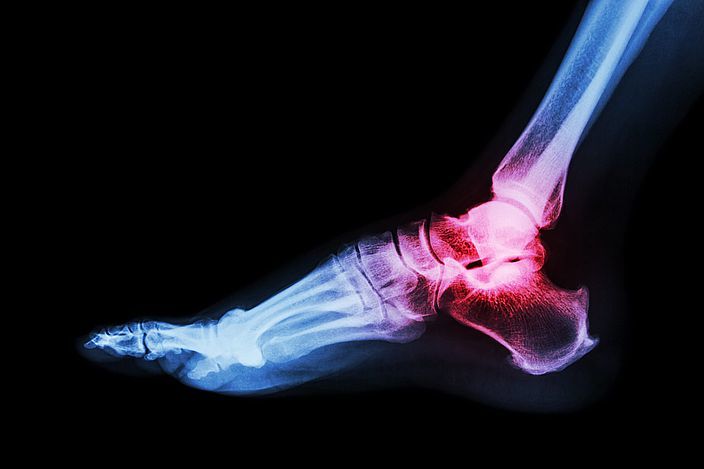

風濕俾大家嘅印象都係番風落雨先會發作,究竟係唔係咁 🤔 ? 病發時帶來痛楚之餘亦為生活帶來不便,中西醫喺風濕治療上可以點舒緩 ?

風濕病成因及病徵

風濕科專科葉文龍醫生指出,風濕病同自身免疫系統紊亂💢有關,係後天因素,身體會產生抗體,攻擊唔同嘅器官,如抗體攻擊自己嘅關節,就會患上類風濕性關節炎 ; 紅斑狼瘡症患者,抗體可能攻擊腎臟、肺或者肝,就會有相對器官炎症發生。

風濕病關節炎同一般勞損唔同

,痛楚會喺早上睡醒或休息過後會更劇烈,甚至有晨僵現象。而勞損性關節炎,休息後通常都可以舒緩症狀。